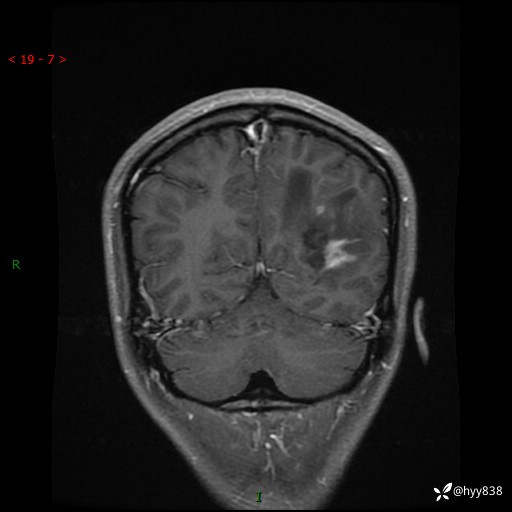

颅脑MRI平扫+增强